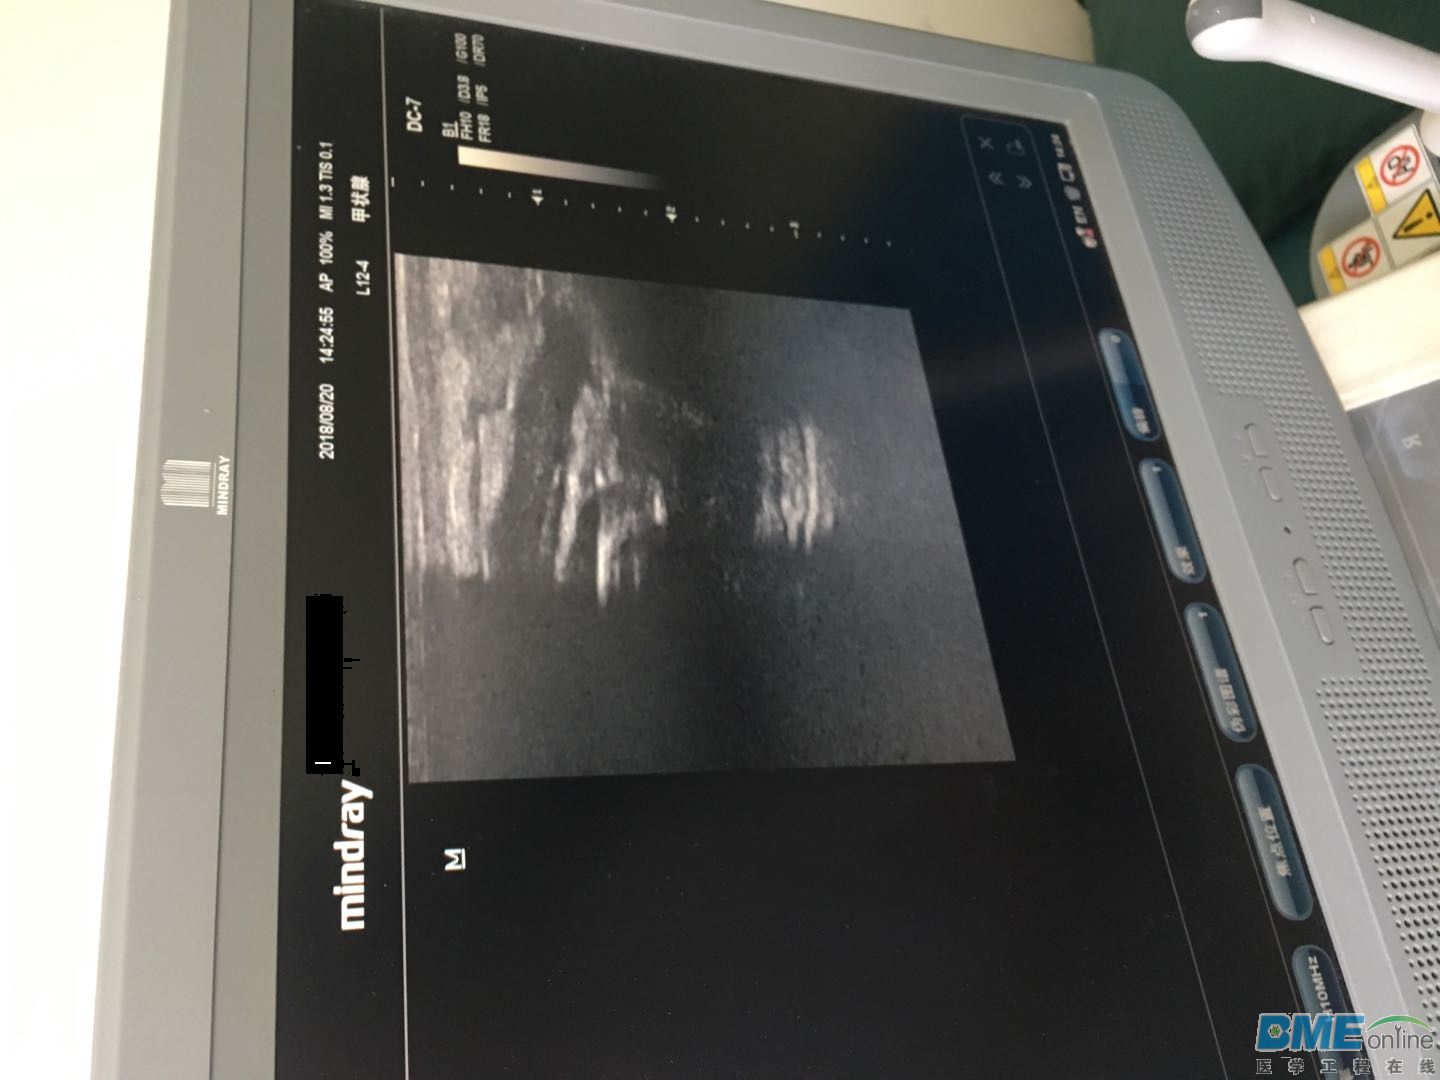

迈瑞DC-7彩超在使用L12-4探头有近一半无回声 ...

迈瑞DC-7彩超在使用L12-4探头有近一半无回声

迈瑞DC-7彩超在使用L12-4探头有近一半无回声,此时给探头一定压力回声又正常,怎么维修?

探头鼓包了,声透镜和匹配层脱胶,建议更换或维修探头,仅供参考